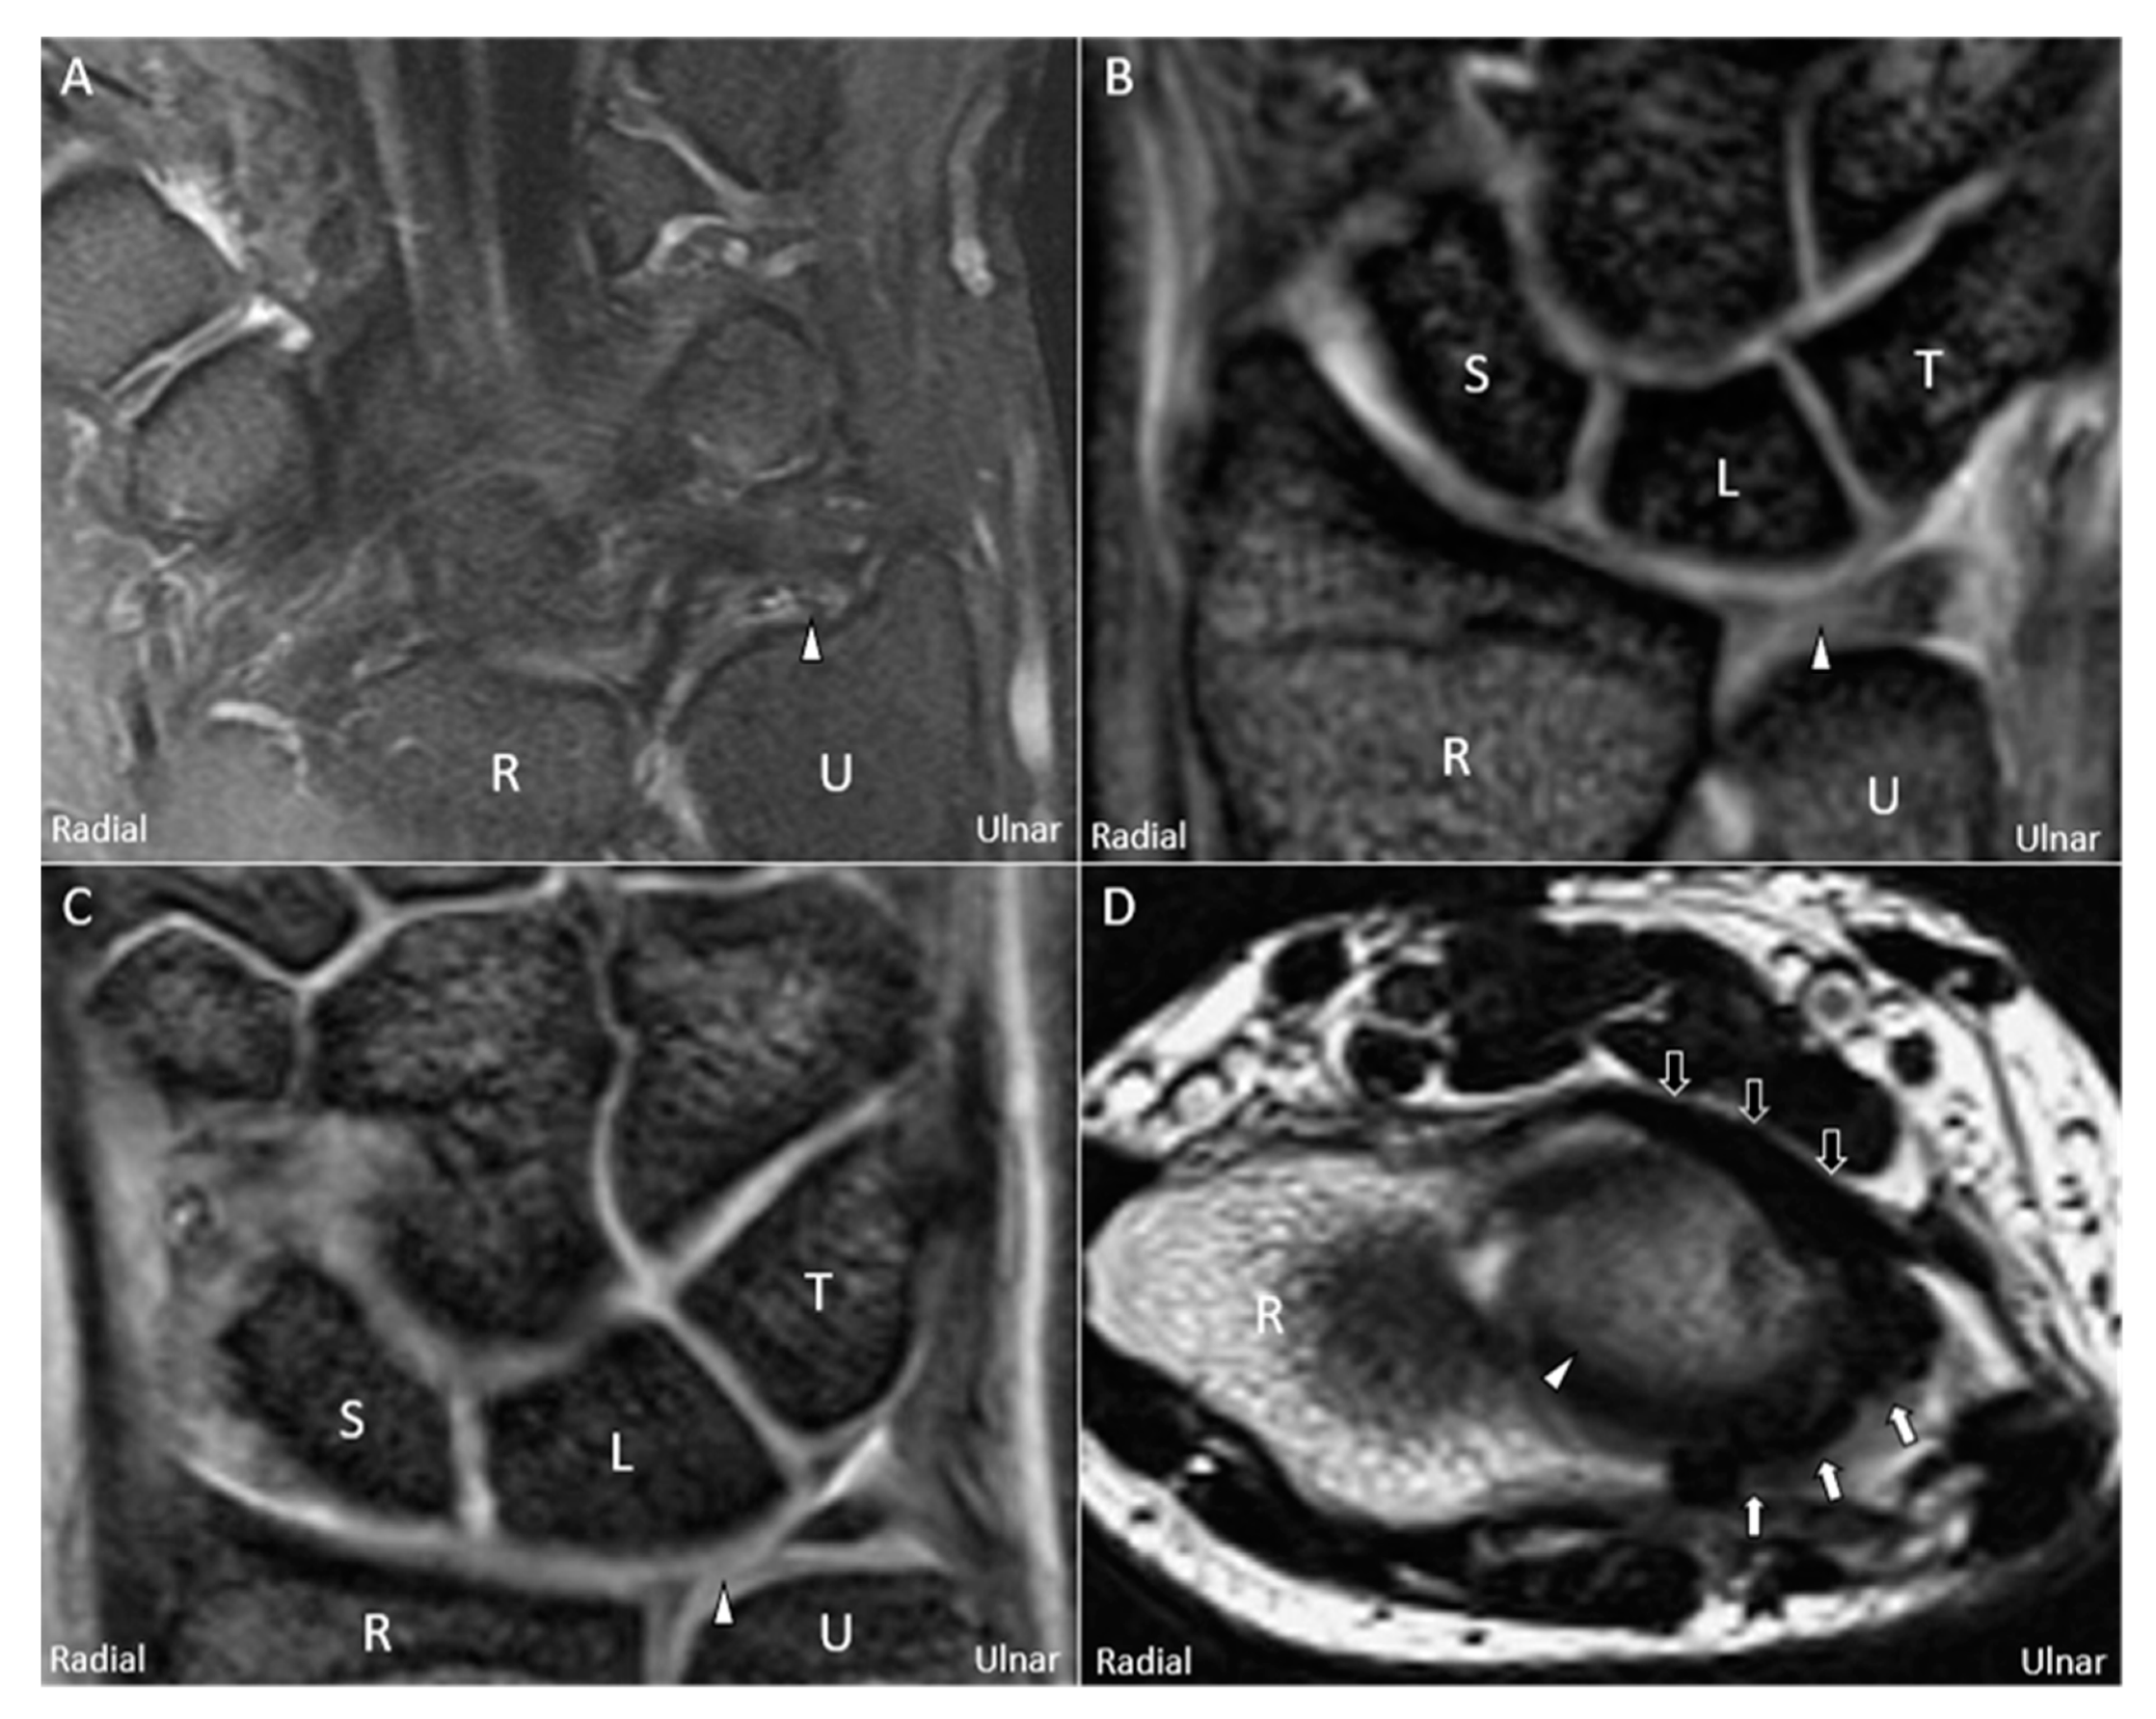

5. Imaging (Other than US)

6. US Imaging